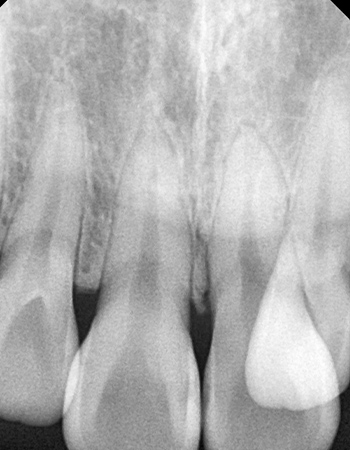

확장 전

확장 후